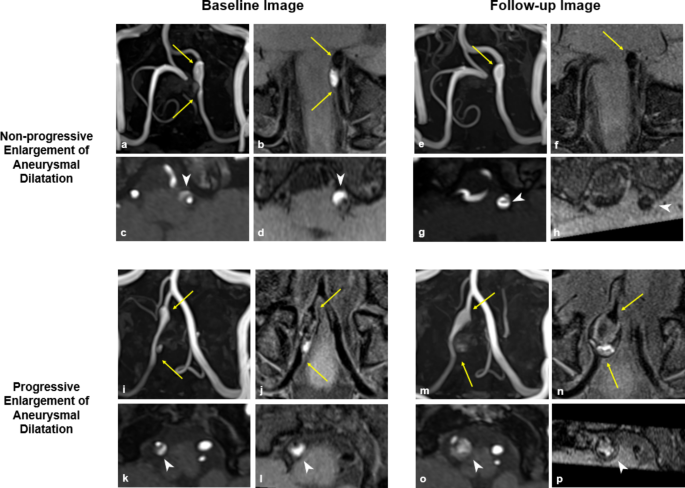

In the IAD lesions that exhibited no further morphological changes, the median time from symptom onset to morphological stability was 3.9 months (95% CI, 3.16–5.5 months) (Fig. 2). Based on these findings, further analyses were conducted on the groups with progressive and non-progressive enlargement of aneurysmal dilatation using the mid-term follow-up imaging performed later than 4 months after the symptom onset. When the groups were compared using imaging taken at a similar time, all four cases in the progressive enlargement group displayed an onion-skin appearance in VW-MRI and intramural hematoma in TOF-MRA. They also demonstrated a larger remodeling index in both VW-MRI (16.56 vs. 2.39, P = 0.021) and TOF-MRA (12.96 vs. 2.01, P = 0.021), and an increased normalized wall index (0.975 vs. 0.67, P = 0.021) and rsIMH (4.6 vs. 1.38, P = 0.021) in VW-MRI (Table 5). Representative cases are displayed in Fig. 3.

Baseline and Follow-up Images in Cases of Non-progressive and Progressive Enlargement of Aneurysmal Dilatation. (a–h) Representative case of non-progressive enlargement of aneurysmal dilatation. (a, b) Baseline images show dissection in the left vertebral artery (arrow) with an increased outer diameter compared to the adjacent normal-looking artery. (c, d) Axial images at the point of maximal outer diameter shows double lumen with dissecting flap and intramural hematoma (arrow head). The remodeling index, normalized wall index, and relative signal intensity of intramural hematoma (rsIMH) were 2.49, 0.59, and 3.09, respectively. (e, f) Follow-up images after 6 months of symptom onset shows residual aneurysmal dilatation of the dissected artery (arrow). (g, h) Axial images demonstrates dissecting flap (arrow head) but no intramural hematoma in both TOF-MRA and VW-MRI. The remodeling index, normalized wall index, and rsIMH were 2.22, 0.64, and 1.33, respectively. (i–p) Representative case of progressive enlargement of aneurysmal dilatation. (i, j) Baseline images show dissection in the right vertebral artery (arrow) with an increased outer diameter. (k, l) Baseline axial images show double lumen with dissecting flap and intramural hematoma (arrow head). The remodeling index, normalized wall index, and rsIMH were 3.43, 0.67, and 3.94, respectively. (m, n) Follow-up images after 6 months of symptom onset show continuous enlargement in the diameter of the dissected artery (arrow). (o, p) Axial images demonstrate the onion-skin appearance of a multilayered hematoma. The remodeling index, normalized wall index, and rsIMH were 26.08, 0.99, and 4.89, respectively.